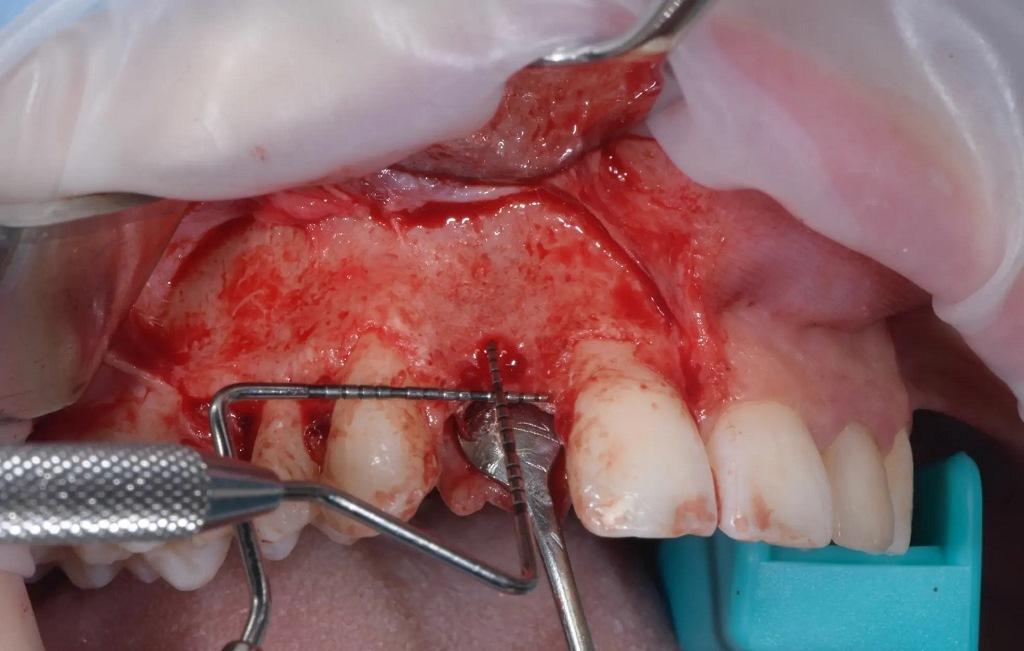

Анестезия проводилась с использованием 4%-ного раствора артикаина с добавлением адреналина в соотношении 1:100 000 (Убистезин, 3M ESPE). С помощью лезвия №15с был сделан поперечный разрез на ороговевшей слизистой оболочке и поднят лоскут на всю толщину. Вертикальные разрезы были сделаны на расстоянии двух зубов друг от друга, как мезиально, так и дистально (фото 4).

Фото 4: Процедура вертикальной регенерации костной ткани после восьминедельного периода заживления.

Реципиентная зона была обработана, и из ипсилатеральной части нижней челюсти (наружного косого гребня) с помощью костного скребка MICROSS (META) была извлечена аутогенная кортикальная кость. На небной стороне дефекта была закреплена резорбируемая коллагеновая мембрана OssMem Hard (Osstem Implant). В дефект была помещена смесь аутогенной кости и неорганической бычьей кости A-Oss Osstem Implant), составленная один к одному; размер частиц: 0,25-1,00 мм; всего 0,5 г. Затем мембрану закрепили двумя дополнительными крепежными винтами.